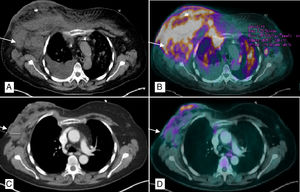

Se realiza biopsia de lesiones de mama que evidencian espongiosis epidérmica con células pequeñas de núcleos irregulares, escaso citoplasma y positividad predominantemente CD4 compatible con LNH de células T CD30+ (HTLV−). En PET/TAC (figs. 1A y B) se evidencia afectación subcutánea en ambas mamas, múltiples adenopatías supra e infradiafragmáticas, esplénicas y pulmonares en relación con el síndrome linfoproliferativo en progresión. Se decide iniciar tratamiento paliativo (metilprednisolona, ciclofosfamida, etopósido y procarbazina) con excelente respuesta, por lo que se decide alta hasta recuperación hematológica. Dos meses después suspende tratamiento por neutropenia febril y acude a urgencias con sobreinfección del tejido mamario y necrosis completa de la misma (fig. 2A).

PET/TAC tórax. A) Múltiples adenopatías axilares bilaterales, la mayor derecha de 4cm (flecha), con afectación subcutánea de ambas mamas con predominio derecho y derrame pleural ipsilateral. B) Captación patológica de 18F-FDG (fluorodeoxiglucosa) en mama derecha, izquierda, cisura menor derecha y parénquima pulmonar bilateral (nódulos milimétricos) en relación con la infiltración linfomatosa. C) Disminución en el tamaño global de mama derecha con burbujas de aire en su interior en relación con la necrosis y la reducción de adenopatías axilares, la mayor derecha de 2,9cm. D) Mejoría morfo-metabólica de la afectación adenopática, pulmonar y en tejido celular subcutáneo sugerente de buena respuesta al tratamiento.

Se ingresa y tras recuperación hematológica, reinicia esquema presentando mejoría radiológica (figs. 1C y D) y delimitación de la necrosis decidiéndose mastectomía higiénica para mejorar el control local de los síntomas. Durante la cirugía se observa desprendimiento casi completo de la glándula, de consistencia pétrea por la necrosis y con material purulento en su interior (fig. 2B). Se realiza mastectomía simple con extirpación parcial del pectoral mayor y menor en algunas zonas más afectadas por la necrosis, eliminándose a su vez varias lesiones en región esternal y descartándose una reconstrucción inmediata debido al proceso infeccioso y al difícil control sistémico de la enfermedad.